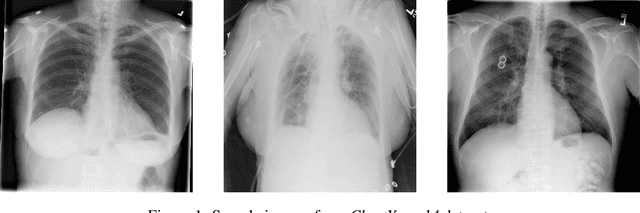

Abstract:Recent advances in deep learning have led to a promising performance in many medical image analysis tasks. As the most commonly performed radiological exam, chest radiographs are a particularly important modality for which a variety of applications have been researched. The release of multiple, large, publicly available chest X-ray datasets in recent years has encouraged research interest and boosted the number of publications. In this paper, we review all studies using deep learning on chest radiographs, categorizing works by task: image-level prediction (classification and regression), segmentation, localization, image generation and domain adaptation. Commercially available applications are detailed, and a comprehensive discussion of the current state of the art and potential future directions are provided.